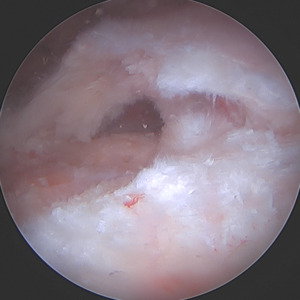

For the primary repair, a double row repair was completed. Medial anchor placement and fixation needed special consideration due to poor bone quality as a result of the subchondral cyst. To support anchor fixation, a calcium phosphate substitute (Tactoset® by Anika Therapeutics) was injected under direct visualization into the subchondral cyst and allowed to set for approximately 10 minutes. One triple-loaded medial row anchor (Healix Advance™ with Dynacord™ by DePuy Synthes) was then placed into the greater tuberosity. Six sutures were passed through the rotator cuff and tied in standard arthroscopic fashion after which two lateral row anchors (X-Twist™ by Anika Therapeutics) were placed to complete a double-row fixation of the rotator cuff tear.

Encountering a subchondral cyst intraoperative can be rather challenging. Do you opt for a larger anchor, buddy anchor, or a suboptimal location for the anchor? Furthermore, the question of anchor pull out may dictate the patient ‘go slow’ during the initial rehabilitation process leading to increased stiffness and pain. I decided to use calcium phosphate to augment at time of surgery prior to anchor placement because I wanted excellent anchor strength for anchor placement due to the diagnosis of a subchondral edema. This substantially increases the immediate pull-out strength of the anchor and allows me to continue my standard post operative rehabilitation protocol.

A medial row anchor was then inserted into the site of calcium phosphate placement with excellent bony purchase. This anchor is loaded with dynamic sutures that self-tension for continuous compression for at least 12 weeks. Two vented anchors (X-Twist 4.5mm PEEK) were then placed laterally to complete the double row repair. The moderate size tear with mild retraction of the tendon drove my decision to complete a double row repair. Double row repairs have been shown to have improved mechanical strength, contact pressure on the repair site, and rotator cuff footprint restoration. The dynamic nature of the sutures is especially important for retracted tears to help maintain the contact pressure to the tuberosity during the initial stages of healing. Any laxity in the suture can lead to increased retear rates.